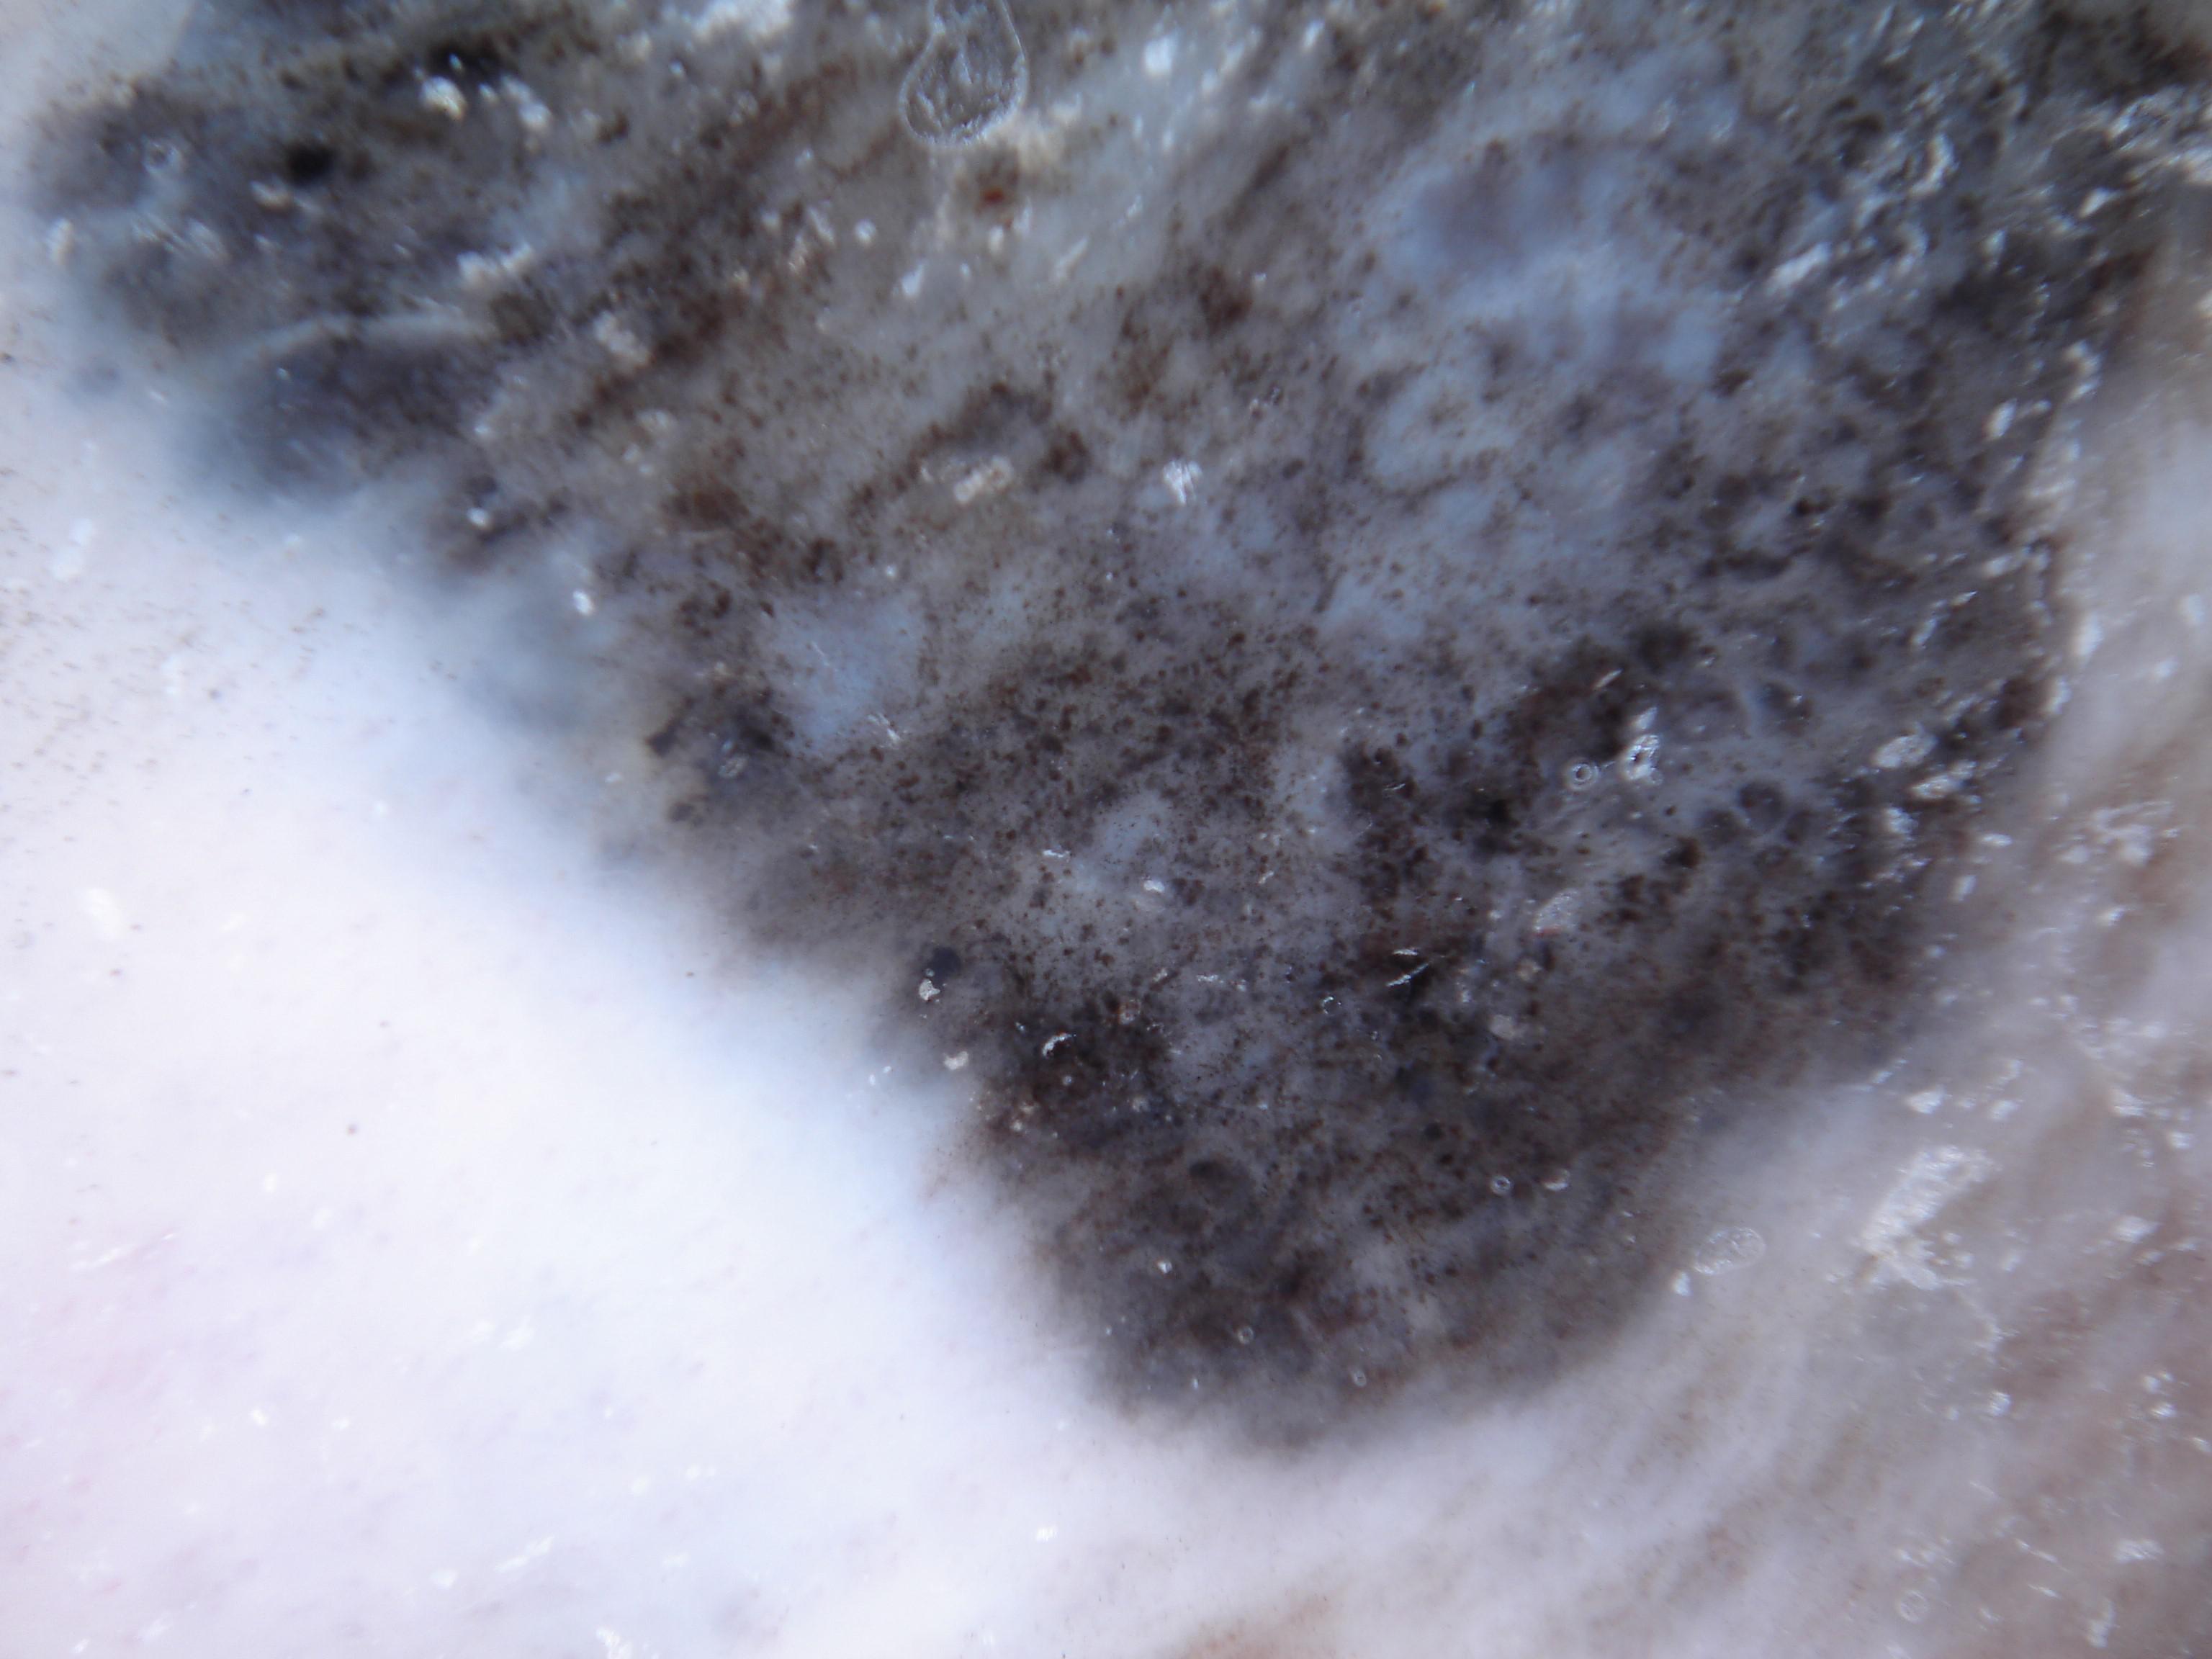

{

"age_approx": 85,

"anatom_site_general": "lower extremity",

"concomitant_biopsy": true,

"dermoscopic_type": "contact non-polarized",

"diagnosis_1": "Malignant",

"diagnosis_2": "Malignant melanocytic proliferations (Melanoma)",

"diagnosis_3": "Melanoma in situ",

"diagnosis_confirm_type": "histopathology",

"family_hx_mm": false,

"image_type": "dermoscopic",

"mel_thick_mm": "0.00",

"melanocytic": true,

"patient_id": "IP_9183698",

"personal_hx_mm": false,

"sex": "male"